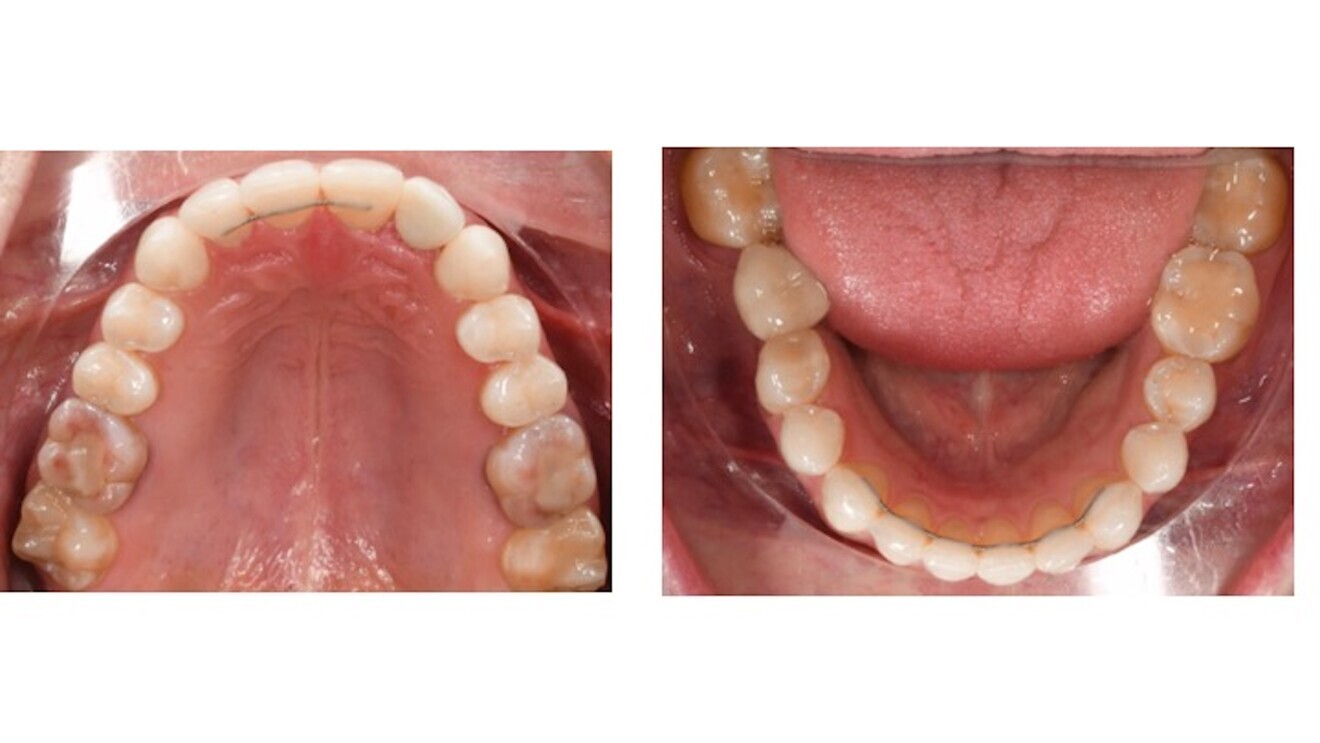

Figs. 11a & b: Occlusal photographs after orthodontic treatment.

The panoramic radiograph after orthodontic treatment showed the correct parallelism in the maxillary left anterior region for the implant placement and the convergence of the roots of teeth #44 and 45 (Fig. 9), but we decided not to spend extra treatment time on the latter, since the patient was really pleased with the result at that point. After completion of orthodontic treatment, perfect Class I molar and canine relationships had been achieved and the midlines were coincident. A temporary crown was placed on the single implant (Figs. 10 & 11), and prosthetic restoration of tooth #12 and final restoration of the implant were completed. An excellent final result was achieved. The soft tissue in the implant area had completely healed, contributing to the high-level aesthetics achieved (Figs. 12–15).